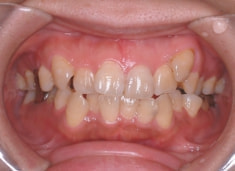

治療前

治療後(2年5ヶ月後)